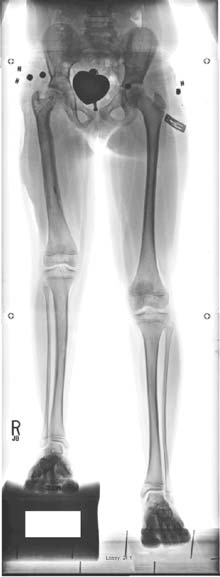

帕利等人(2013年)进行了一项回顾性单中心研究,基于某单一中心三位外科医生的经验[19]报告PRECICE系统的早期结果。本研究已获得机构审查委员会批准。结果首次于2013年4月在希腊雅典举行的欧洲小儿骨科学会年会上发表,随后在加拿大多伦多的北美小儿骨科学会(POSNA)上发表。该研究最近已发表[20]。作者回顾了2011年12月1日至2012年12月4日期间植入的48例连续患者(65个PRECICE钉)的结果(均为PRECICE 1)。本系列患者的平均年龄为25.6岁(10.3–58.4岁)。23名患者因先天性不等长(FIGURE 5)进行了延长;平均年龄为18.5岁(10.3–43.7岁),术前平均延长目标为4.91厘米(1.5–6.5厘米),而术前平均下肢长度差异为6.27厘米(1.5–18.2厘米)。延长速率为0.8毫米/天。除五名患者外,该组所有患者均达到了延长目标;平均延长长度为4.5厘米(0.5–6.5厘米)(FIGURES 6& 7)。四名患者因发育性不等长进行了延长;平均年龄为17.8岁(13–27岁),术前平均延长目标为3.68厘米(1.5–6.5厘米)。延长速率为1毫米/天。平均延长长度为3.68厘米(1.5–6.5厘米)。所有患者均无并发症地实现了术前延长目标。六名患者因创伤后肢体长度差异(FIGURE 8)进行了延长;术前平均目标为3.48厘米(1.7–5.0厘米),平均年龄为

术前前后位和侧位X光片。她既往曾接受超级髋‐超级膝手术,并在4岁时成功接受过一次外固定器延长术。她的腿部长度差异为7厘米。(B) 使用PRECICE 2 8.5毫米 245毫米、转子入路股骨钉进行5厘米延长后的前后位X光片。同时使用半骨骺阻滞板治疗其膝外翻。(C) 此为牵张停止一个月后愈合期的前后位X光片,显示牵开间隙正在由骨组织填充。)